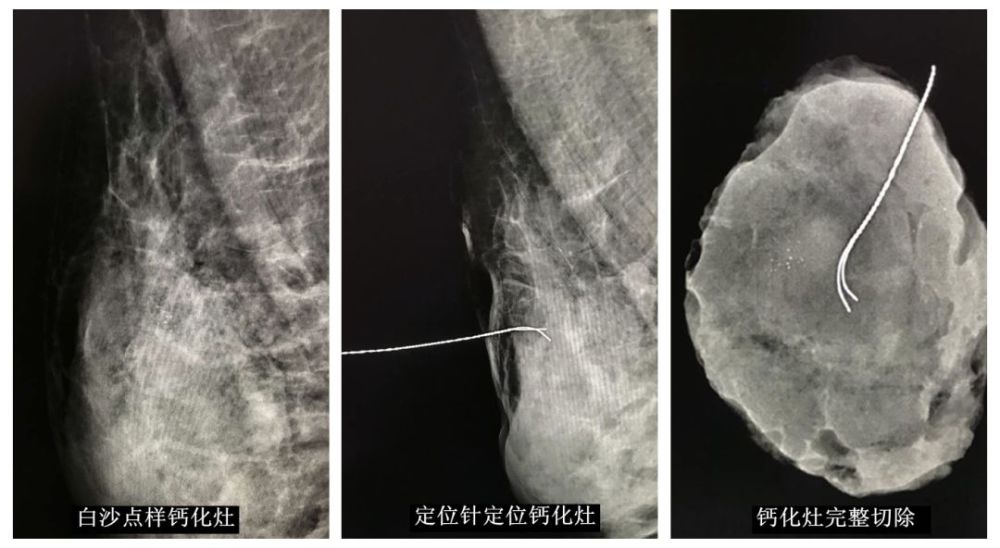

乳腺内异常钙化灶导丝定位活检

600x571 - 58KB - JPEG

513x600 - 43KB - JPEG

600x457 - 30KB - JPEG